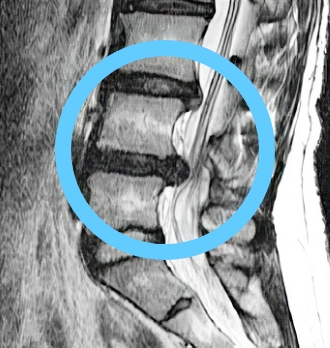

치료 후 탈출된 디스크

10년간 지속적 흡수

탈출된 디스크가 치료 후 10년간 지속적으로 감소, 10년 후에는 약 2/3 가까이 거의 흡수됨

비수술 한방통합치료 치료 10년 후

탈출된 디스크가 흡수된 모습

치료 전 (2007)

10년 경과 (2018)

※ 환자분에게 사전 동의를 받아 동일 조건에서 촬영되었으며, 개인에 따라 치료 후 부작용이 발생할 수도 있으니 의료진과 상담 후 치료를 진행하시기 바랍니다.